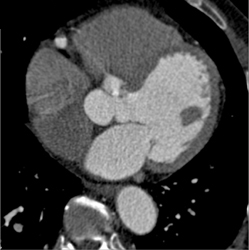

Diseased LAD and Circumflex Artery (CX)